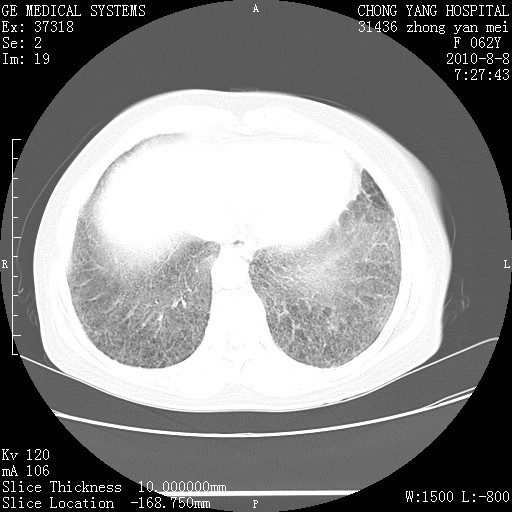

标题: CT28269:F62Y咳嗽胸痛数月。 [打印本页]

标题: CT28269:F62Y咳嗽胸痛数月。

两肺弥漫性间质纤维化伴继发性支扩。

考虑两肺间质性肺炎并肺间质纤维化。

肺间质纤维化合并感染

双肺间质纤维化合并感染、肺气肿

两肺间质纤维化并牵拉性细支气管扩张。

考虑两肺间质性肺炎并肺间质纤维化,肺气囊形成。